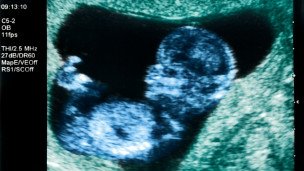

عکس آرشیوی است

مقامات بیمارستانی در جنوب ترکیه گفتهاند زنی که برای اولین بار موفق به دریافت رحم پیوندی از یک اهدا کننده شده بود، هم اکنون باردار است.

پزشکان هم اکنون اعلام کردهاند که در پی انتقال جنین به رحم این زن، که از راه آی وی اف (IVF) یا لقاح مصنوعی تشکیل شده بود ، او نزدیک به دو هفته باردار است.